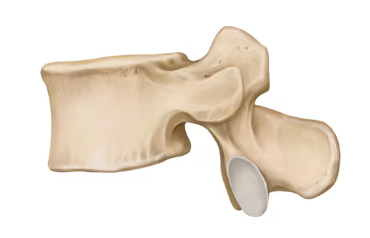

Lumbar vertebra

Superior articular process

Transverse process

Inferior articular facet

Superior articular facet

Lamina

Pedicle

Vertebral foramen